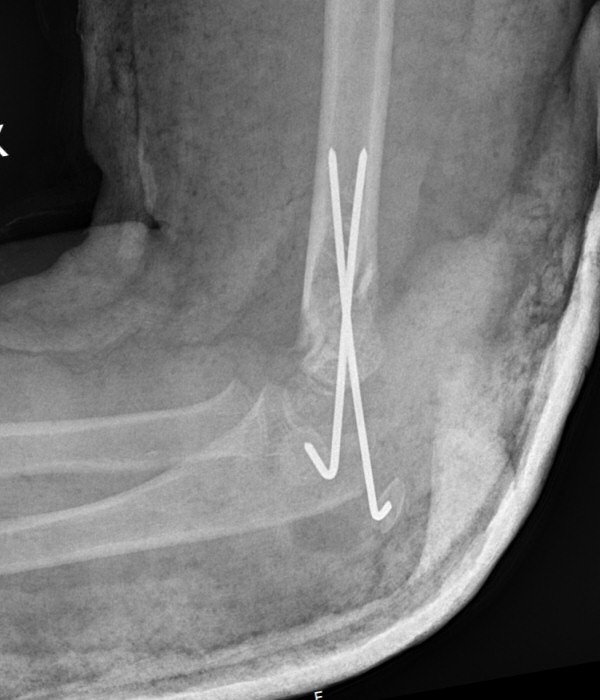

Suprakondylär humerusfraktur, Gartland 2, opererades med stiftning